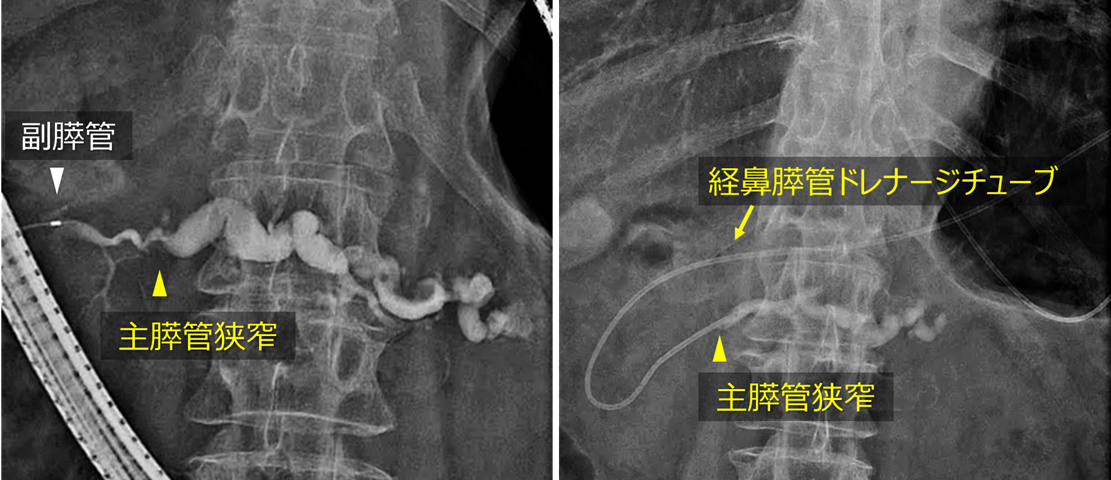

診断が得られなかったため、続いてEUSを行いました。主膵管途絶部に淡い低エコー領域を認めたため(左図)、EUS-FNAを行いました(右図)。その結果、腺癌と診断されました。画像所見から膵上皮内癌(carcinoma in situ)の可能性が高いと考えられたため、術前化学療法は行わず、膵頭十二指腸切除術を施行しました。手術後の病理診断では、膵上皮内癌(Stage 0)と診断されました。

EUS

左:膵管狭窄部の周囲に淡い低エコー領域を認めます。

右:慎重にこの低エコー領域を穿刺しました。